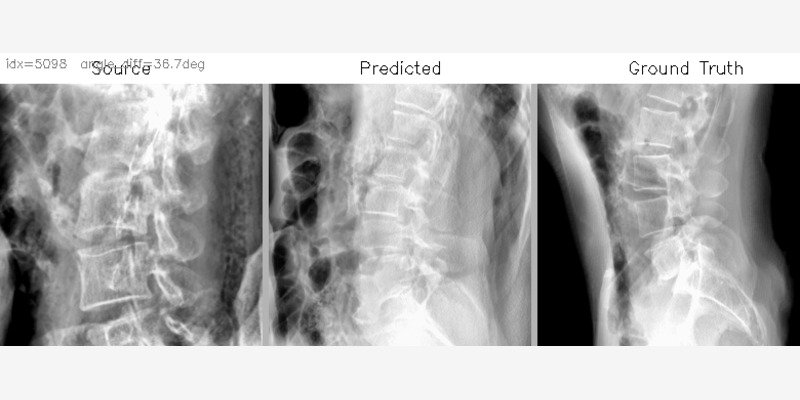

research 椎弓根螺钉轨迹自动规划 覆盖完整胸腰椎的手术路径规划流水线,处理 742 例患者 CT 数据 动作条件化术中 X 射线视角预测 基于条件扩散模型的 C 臂手术视角规划 course M — 咖啡馆社交机器人 基于 GPT-4o 的情感陪伴社交机器人,部署于真实咖啡馆环境 WearWise — AI 穿搭推荐 个人云端衣橱,支持 AI 穿搭推荐与虚拟试穿